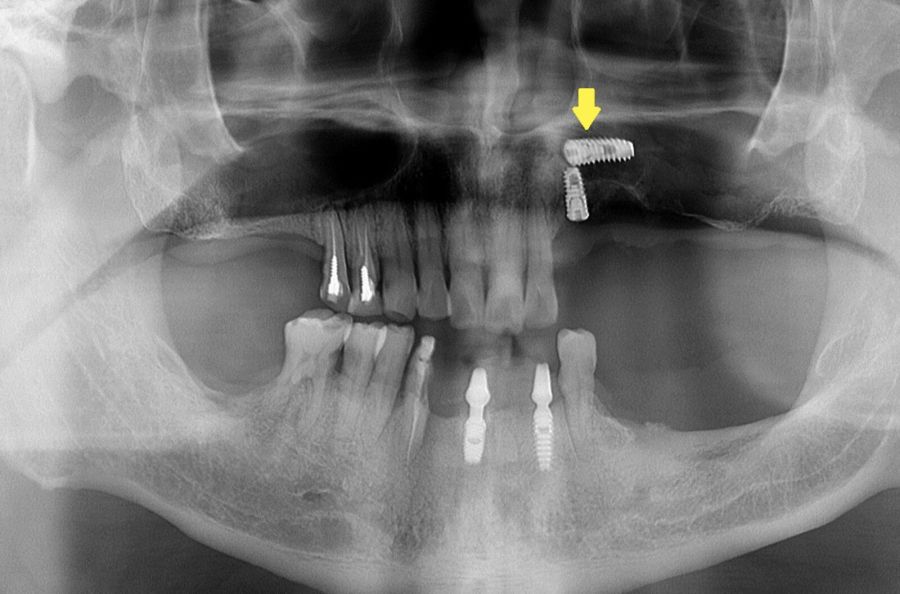

缺牙已久,一名63歲的男子,日前好不容易在住家附近的診所接受了左側上顎多顆人工植牙手術,沒想到手術後卻連發高燒,左側臉頰嚴重腫脹,赴醫院就醫才知道是人工牙根意外滑入左側鼻竇內,如果未及時處理,恐引發排感染甚至有失明的可能。

原來該名男子是因為長期缺牙以及患有糖尿病的原因,上顎骨較薄,植牙時需要同時進行鼻竇增高手術,沒想到就在手術過程中,由於齒槽骨過於鬆軟,導致人工牙根滑入鼻竇。

何承翰指出,如果在植牙手術前未充分評估齒槽骨的厚度,人工牙根有可能穿過鼻竇,導致鼻竇炎或異物感,一旦異物掉入鼻竇又未及時處理,將有感染蜂窩性組織炎的可能,要是細菌沿著鼻竇上緣進入眼眶,更不排除眼窩感染甚至失明的可能。

感染通常發生在異物掉入的三到五天內發生。以該名男子為例就十分典型,臉頰在第五天開始感到腫脹和疼痛,醫師進行清創手術時也在鼻竇看到膿液因此一併清創。